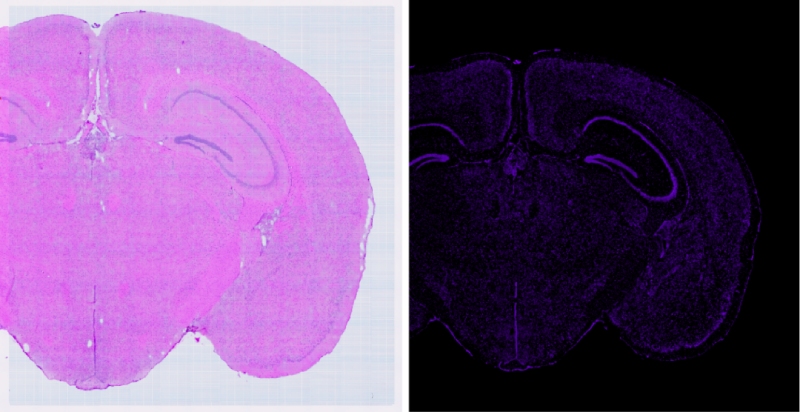

在生命科學的探索之旅中,技術(shù)的每一次革新都是我們深入理解生命奧秘的堅實基石。百邁客生物推出顯微掃描儀領(lǐng)域的旗艦力作——BH1000掃描儀,它將引領(lǐng)我們邁入空間組學成像的新紀元。BH1000掃描儀不僅可以實現(xiàn)人體、動物、植物以及各類玻片標本的快速全切片掃描成像,更以其卓越的性能全面滿足百創(chuàng)空間組學實驗的高端成像需求。其可以實現(xiàn)明場以及熒光的原片高清無錯成像,結(jié)合百創(chuàng)S空間系列細胞分割算法,能夠?qū)崿F(xiàn)精準的空間單細胞分割,為空間組學細胞層面的研究提供了強有力的支持。

在樣本完成質(zhì)檢并合格后,需要對研究的目標區(qū)域進行確認,可以利用BH1000進行高清(標配高品質(zhì)平場復消色差物鏡,20×物鏡,數(shù)值孔徑N.A.≥0.8,?同時最多支持拓展4個物鏡)的明場成像來進行判斷。

通過BH1000快速(20X,8mm*8mm,小于50S)得到高清明場圖像與高清的熒光(支持7個熒光通道,各通道有獨立傳感器,電動切換,標配明場、?DAPI、FITC和CY3)成像結(jié)果來選擇最優(yōu)的透化時間(需要選擇熒光最亮且符合相應明場結(jié)構(gòu)無明顯逸散的梯度)

可以利用BH1000對明場及熒光掃描過程中經(jīng)常出現(xiàn)的拼接錯誤進行校準(自主研發(fā)BMCHiper軟件,搭配自研半透半返模塊,實現(xiàn)圖像無錯校準),得到原片無錯高清的熒光圖像與原片無錯高清的明場圖像,為后續(xù)空間數(shù)據(jù)準確的定位和可視化提供基礎(chǔ),使得復雜的轉(zhuǎn)錄組數(shù)據(jù)能夠轉(zhuǎn)化為最直觀,最精準的生物學見解。